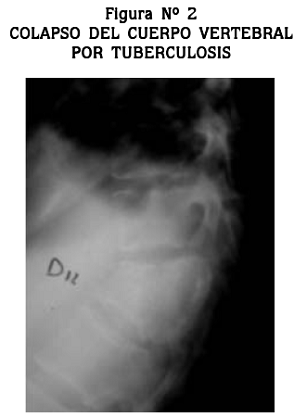

La destrucción del cuerpo vertebral fue el hallazgo radiológico más frecuente; estaba presente en 20 pacientes (57.1%); otros hallazgos fueron la osteopenia en 11 (31.4%) y la disminución del espacio articular en 15 (42.9%) (Figura Nº 2).

El compromiso limitado por disminución del espacio intervertebral sin colapso vertebral se presentó en 5 de los 35 pacientes (14.3%). Siete pacientes (20%) tenían antecedentes de TB pero no fue posible precisar el tratamiento que habían recibido ni el seguimiento que se les había hecho.